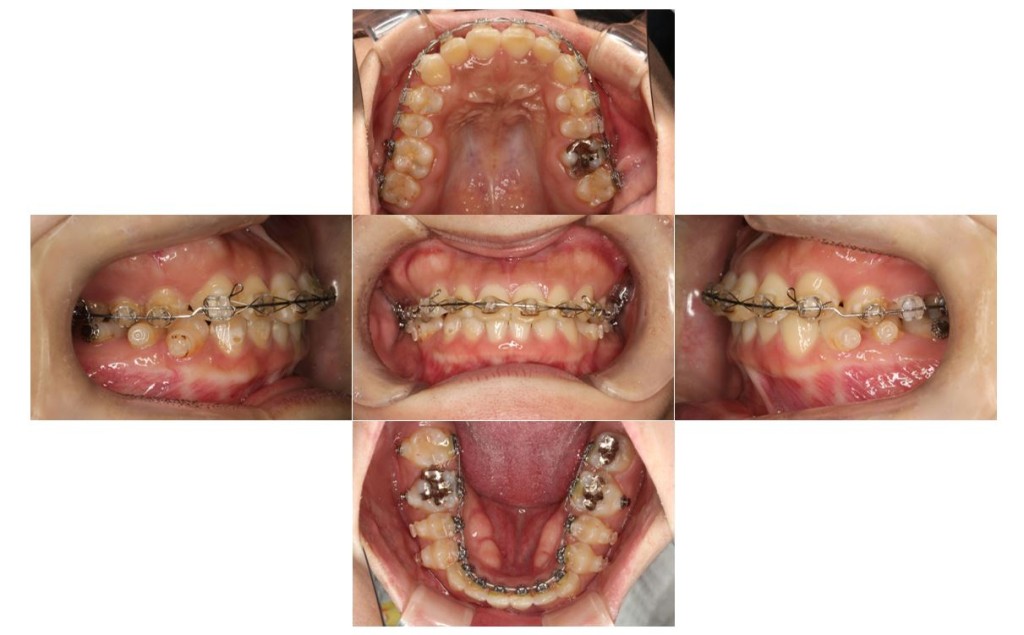

【1年後】

当院の症例

| 主訴 | ずっと気になっていた見た目、噛み合わせを含めて受け口を治したい。期間はかかってもいいので、外科手術をしないで歯列矯正だけで改善したい。 |

| 治療期間 | 3年6ヶ月40回 |

| 矯正の装置 | 裏側矯正から治療途中に表側矯正へ変更 |